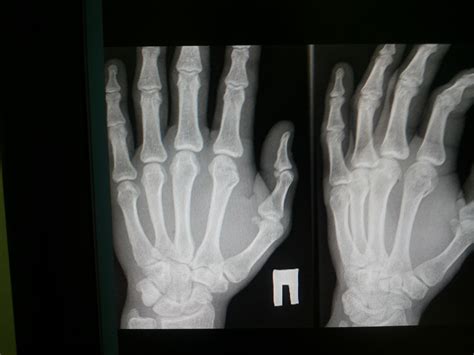

If you suspect you have a sprained or broken finger, it's important to seek medical attention promptly. A healthcare professional can perform a thorough examination and order imaging tests, such as X-rays, to confirm the diagnosis and determine the best course of treatment.